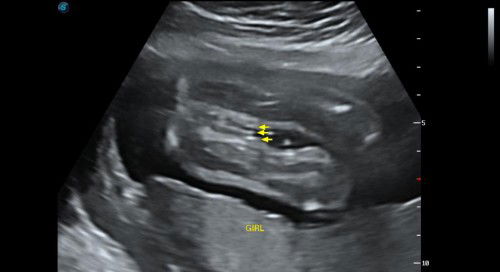

Betul ke jantina girl

Hi mommy.. maaf ye pic tak berape jelas..betul ke ni jantina girl..

sy pn scan mcm ni jgk 3line mmg ggirl ni....sy scan dr 18 dgn 19mgu ttp sma nmpk 3line....mmg sah la ggirl🤣

nmpak mcam bby girl,klau bby girl agak susah skit nk tau jntina,klau boy senang,pistol dia nmpak je..🤭

Hehe, burger sis, Perempuan tu. Sis scan brpa kali jugak?. Saya kali ke4 bru nmpak. hahah, gugurl jugakk

nampak macam baby girl sbb ada burge dkt situ....

masa anak first saye macam ni. sama. memang girl.

iye ni girl.. tahniah..

Nmpk mcm baby girl

ya girl ada 3 line..